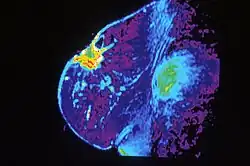

Scintimammography is a type of breast imaging test that is used to detect cancer cells in the breasts of some women who have had abnormal mammograms, or for those who have dense breast tissue, post-operative scar tissue or breast implants, but is not used for screening or in place of a mammogram. Rather, it is used when the detection of breast abnormalities is not possible or not reliable on the basis of mammography and ultrasound. In the scintimammography procedure, a woman receives an injection of a small amount of a radioactive substance called technetium 99 sestamibi. This substance is preferably taken up by cancerous tissues, making them show brightly on the images.[44] Research has also shown that Tc-99 Sestamibi wash out rate is a reliable test for predicting tumor response to neoadjuvant chemotherapy in locally advanced breast cancer.[45]